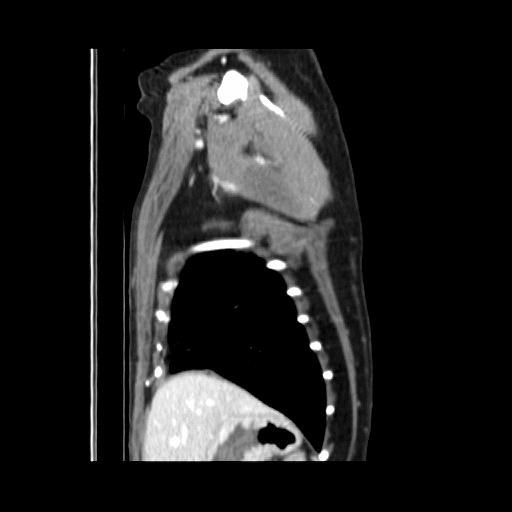

엑스레이 사진과 CT 사진(흉부 앞, 우측 옆)은 첨부하였습니다.

폐 우측 위쪽에 원발성 암이 발생한 것으로 보였습니다.

식도와 심장을 눌러서 기침을 발생시켰습니다.

나쁜 소식은 심장과 혈관이 위치한 안 좋은 부위에 암이 있다는 것이고,

좋은 소식은 심장과 혈관과 아직 붙지 않고 떨어져 있다는 것이었습니다.